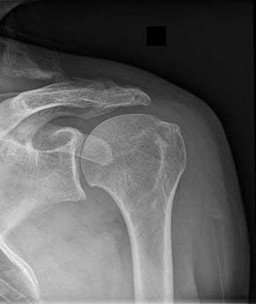

According to recent quantitative anatomical studies utilizing MRI and gadolinium, which of the following vessels provides the principal intraosseous blood supply to the humeral head, challenging historical teachings regarding proximal humerus vascularity?

Correct Answer: Posterior humeral circumflex artery

Historically, the anterior humeral circumflex artery (via its arcuate branch) was thought to be the primary blood supply to the humeral head. However, modern quantitative studies (e.g., Hettrich et al.) have demonstrated that the posterior humeral circumflex artery provides the vast majority (approximately 64%) of the intraosseous blood supply to the humeral head.